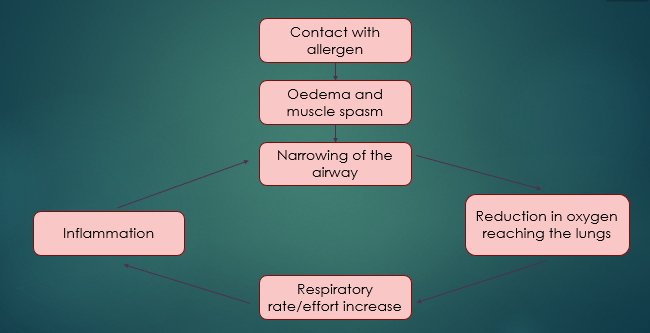

Anaphylaxis

Contact with allergen

Oedema and muscle spasm

Narrowing of the airway

Inflammation OR Reduction in oxygen reaching the lungs

Respiratory rate/effort increases

What is anaphylaxis?

A severe allergic reaction, body reacts, so becomes hypersensitive to a foreign substance

Patient has contact with the allergen - this is usually inhalation but can be caused by something else, such as a wasp/bee sting or blood transfusion reaction

It is in serve cases that we get respiratory distress

After the patient has come into contact with the allergen, Oedema occurs ..

Swelling and muscle spasm

This then causes a narrowing of the airway, so less o2 gets into the body

That’s what compensatory mechanisms kick in = increase respiration effort and rate, but this causes more inflammation and more narrowing

Becomes a vicious cycle of the body trying to correct it but the compensatory mechanisms are increasing the inflammatory response